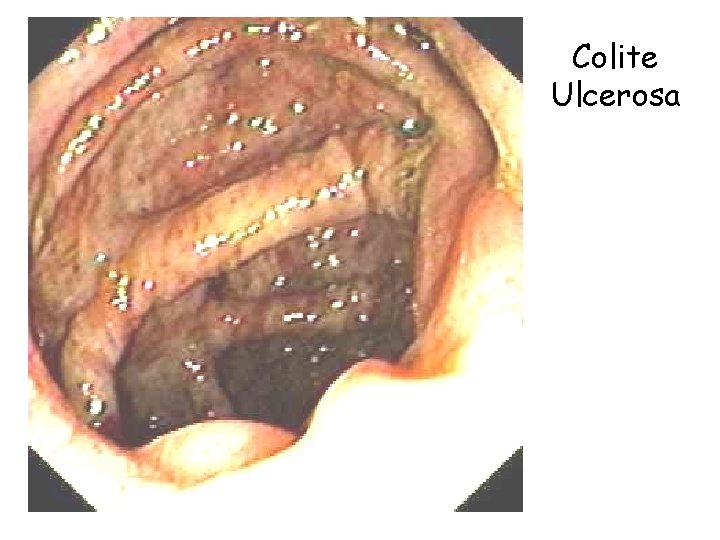

Colite Ulcerosa l l l Diffusione in tutti i paesi In Italia: prevalenza 60 - 70 casi x 100. 000 abitanti Incidenza 5 – 5. 5 casi x 100. 000 abitanti L’incidenza tende a rimanere stabile nei decenni a differenza della Malattia di Crohn Maggiore frequenza di presentazione tra i 20 ed i 40 anni con un secondo picco di frequenza nella sesta – settima decade Uguale prevalenza nei due sessi Anatomia patologica Cancro del colon 18

Colite Ulcerosa – Decorso l Nel 75 % dei casi ha un decorso intermittente l Nel 20 % dei casi ha un decorso cronico continuo l Nelle fasi di remissione le lesioni infiammatorie floride si estinguono Anatomia patologica Cancro del colon 20

Colite ulcerosa – prevenzione del cancro Il rischio di cancerizzazione diviene consistente dopo 8 – 10 anni di malattia ed è maggiore nei pazienti con malattia più estesa l Pertanto i pazienti dovrebbero iniziare un programma di sorveglianza endoscopica l l l Colonscopia ogni 3 anni fino a 20 anni di malattia Colonscopia ogni 2 anni da 20 a 30 anni di malattia Anatomia patologica Cancro del colon 21